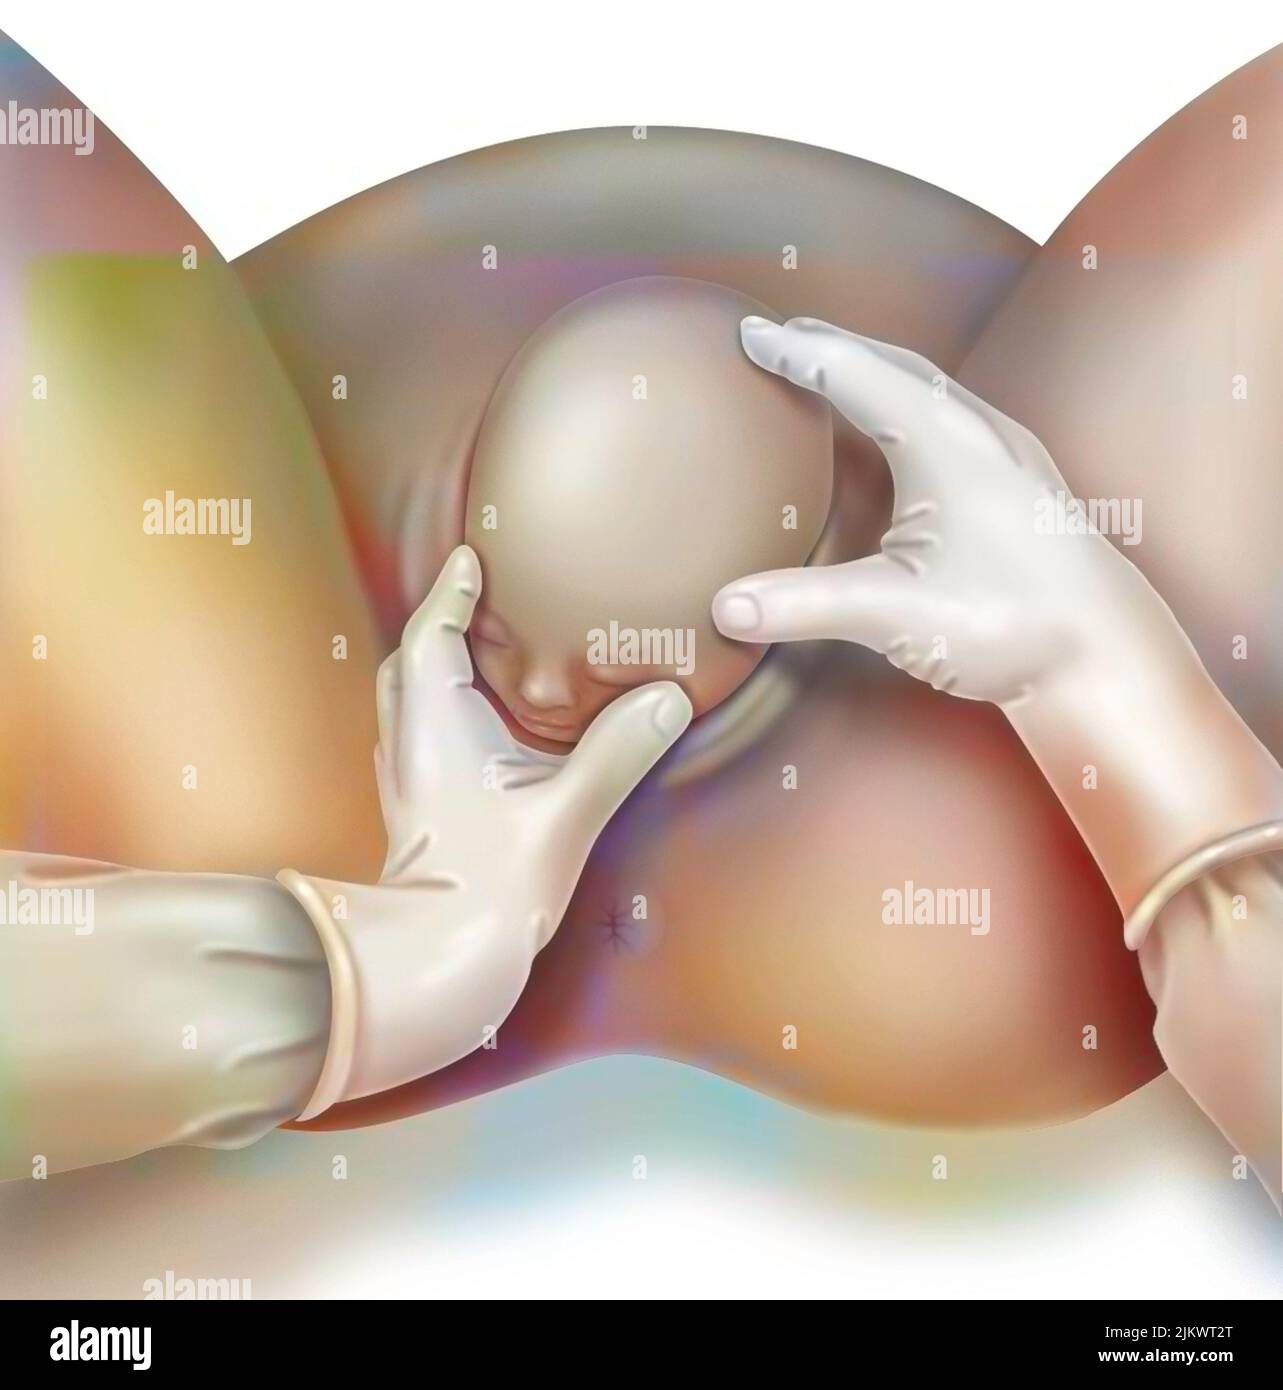

Childbirth, stage 1: the baby is engaged in the pelvis. Stock Photohttps://www.alamy.com/image-license-details/?v=1https://www.alamy.com/childbirth-stage-1-the-baby-is-engaged-in-the-pelvis-image476926081.html

Childbirth, stage 1: the baby is engaged in the pelvis. Stock Photohttps://www.alamy.com/image-license-details/?v=1https://www.alamy.com/childbirth-stage-1-the-baby-is-engaged-in-the-pelvis-image476926081.htmlRF2JKWT29–Childbirth, stage 1: the baby is engaged in the pelvis.

Childbirth, stage 2: the baby's head is out. Stock Photohttps://www.alamy.com/image-license-details/?v=1https://www.alamy.com/childbirth-stage-2-the-babys-head-is-out-image476926096.html

Childbirth, stage 2: the baby's head is out. Stock Photohttps://www.alamy.com/image-license-details/?v=1https://www.alamy.com/childbirth-stage-2-the-babys-head-is-out-image476926096.htmlRF2JKWT2T–Childbirth, stage 2: the baby's head is out.